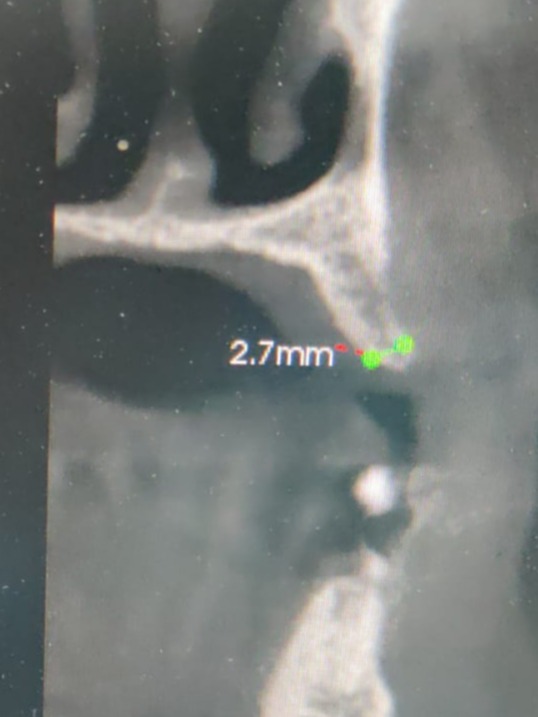

**“I was nervous when I first learned my jawbone was very narrow—just 2.5 mm—and worried about whether an implant would even be possible. Dr. Kedar Bakshi explained the procedure clearly and told me he would be using his special Osseosure system to preserve my bone and make the process more comfortable.

It was really challenging case. Delayed implantation with highly resorbed bone.